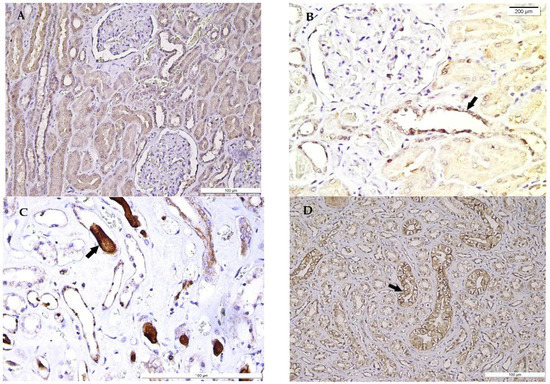

Figure 2.

Sirtuin1 (SIRT1) expression in the myocardium of hypothermia cases. (A) Nuclear SIRT1 strong positivity along with weak cytoplasmic positivity of cardiomyocytes (arrows). (B) Nuclear SIRT1 strong positivity (arrows) along with weak cytoplasmic positivity in myocardial cells. (C) SIRT1 positivity in wavy cardiomyocytes, with focal loss of expression (arrow). (D) SIRT1 positivity in cardiomyocytes, with focal positivity loss associated with contraction bands (arrow), evident in longitudinal incidences.

Increasing evidence shows that SIRT1 is related to cellular hypoxia and heart protection from endoplasmic reticulum stress-related organ damage [29], ageing, myocardial ischemia, and hypertrophy [13]. Scarce literature data are available regarding SIRT1 cardiac expression in victims of hypothermia, due to limitations of large study groups’ collection. The SIRT1 weak cytoplasmic staining of cardiomyocytes containing contraction bands has been noticed in our study group. SIRT1 expression has been lost in specific areas containing contraction bands, in agreement with the results of Morita et al. [30]. This finding has been considered a characteristic immunostaining pattern in hypothermia-related fatalities in comparison with other death causes such as traffic accidents or pneumonia [30]. This feature may be also considered an important tool in hypothermia-related death in forensics, in opposition to death due to myocardial ischemia or infarction, characterised by a lack of SIRT1 expression in modified myocardial tissue [25], in agreement with our results. Our findings may lead to the hypothesis that the myocardial tissue chronic hypoperfusion may be responsible for the patients’ poor prognoses, despite specific therapy, due to the high incidence of pre-existent myocardial ischemic disease, mainly associated with coronary fibrous cap atheroma. The constant finding of contraction bands, associated with the focal loss of SIRT1 expression, has demonstrated the impossibility of heart-appropriate reperfusion in the examined microscopic sections.

Myocardial weak and heterogeneous SIRT1 expression represents a constant finding in hypothermia. Supplementarily, SIRT1 loss in specific areas of cardiomyocytes showing contraction bands can be associated with its intervention in cold stress. SIRT1 loss may suggest its focal depletion in severe hypoxia determined by prolonged exposure to low ambient temperatures.